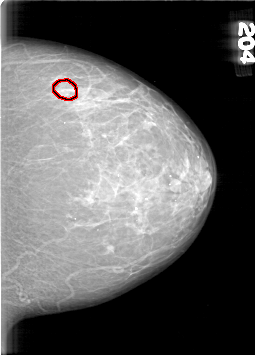

D_4098_1.LEFT_CC

LEFT_CC LINES 6391 PIXELS_PER_LINE 4591 BITS_PER_PIXEL 12 RESOLUTION 43.5 OVERLAY

FILE: D_4098_1.LEFT_CC.OVERLAY

TOTAL_ABNORMALITIES 1

ABNORMALITY 1

LESION_TYPE CALCIFICATION TYPE AMORPHOUS DISTRIBUTION CLUSTERED

ASSESSMENT 0

SUBTLETY 3

PATHOLOGY BENIGN

TOTAL_OUTLINES 1

BOUNDARY